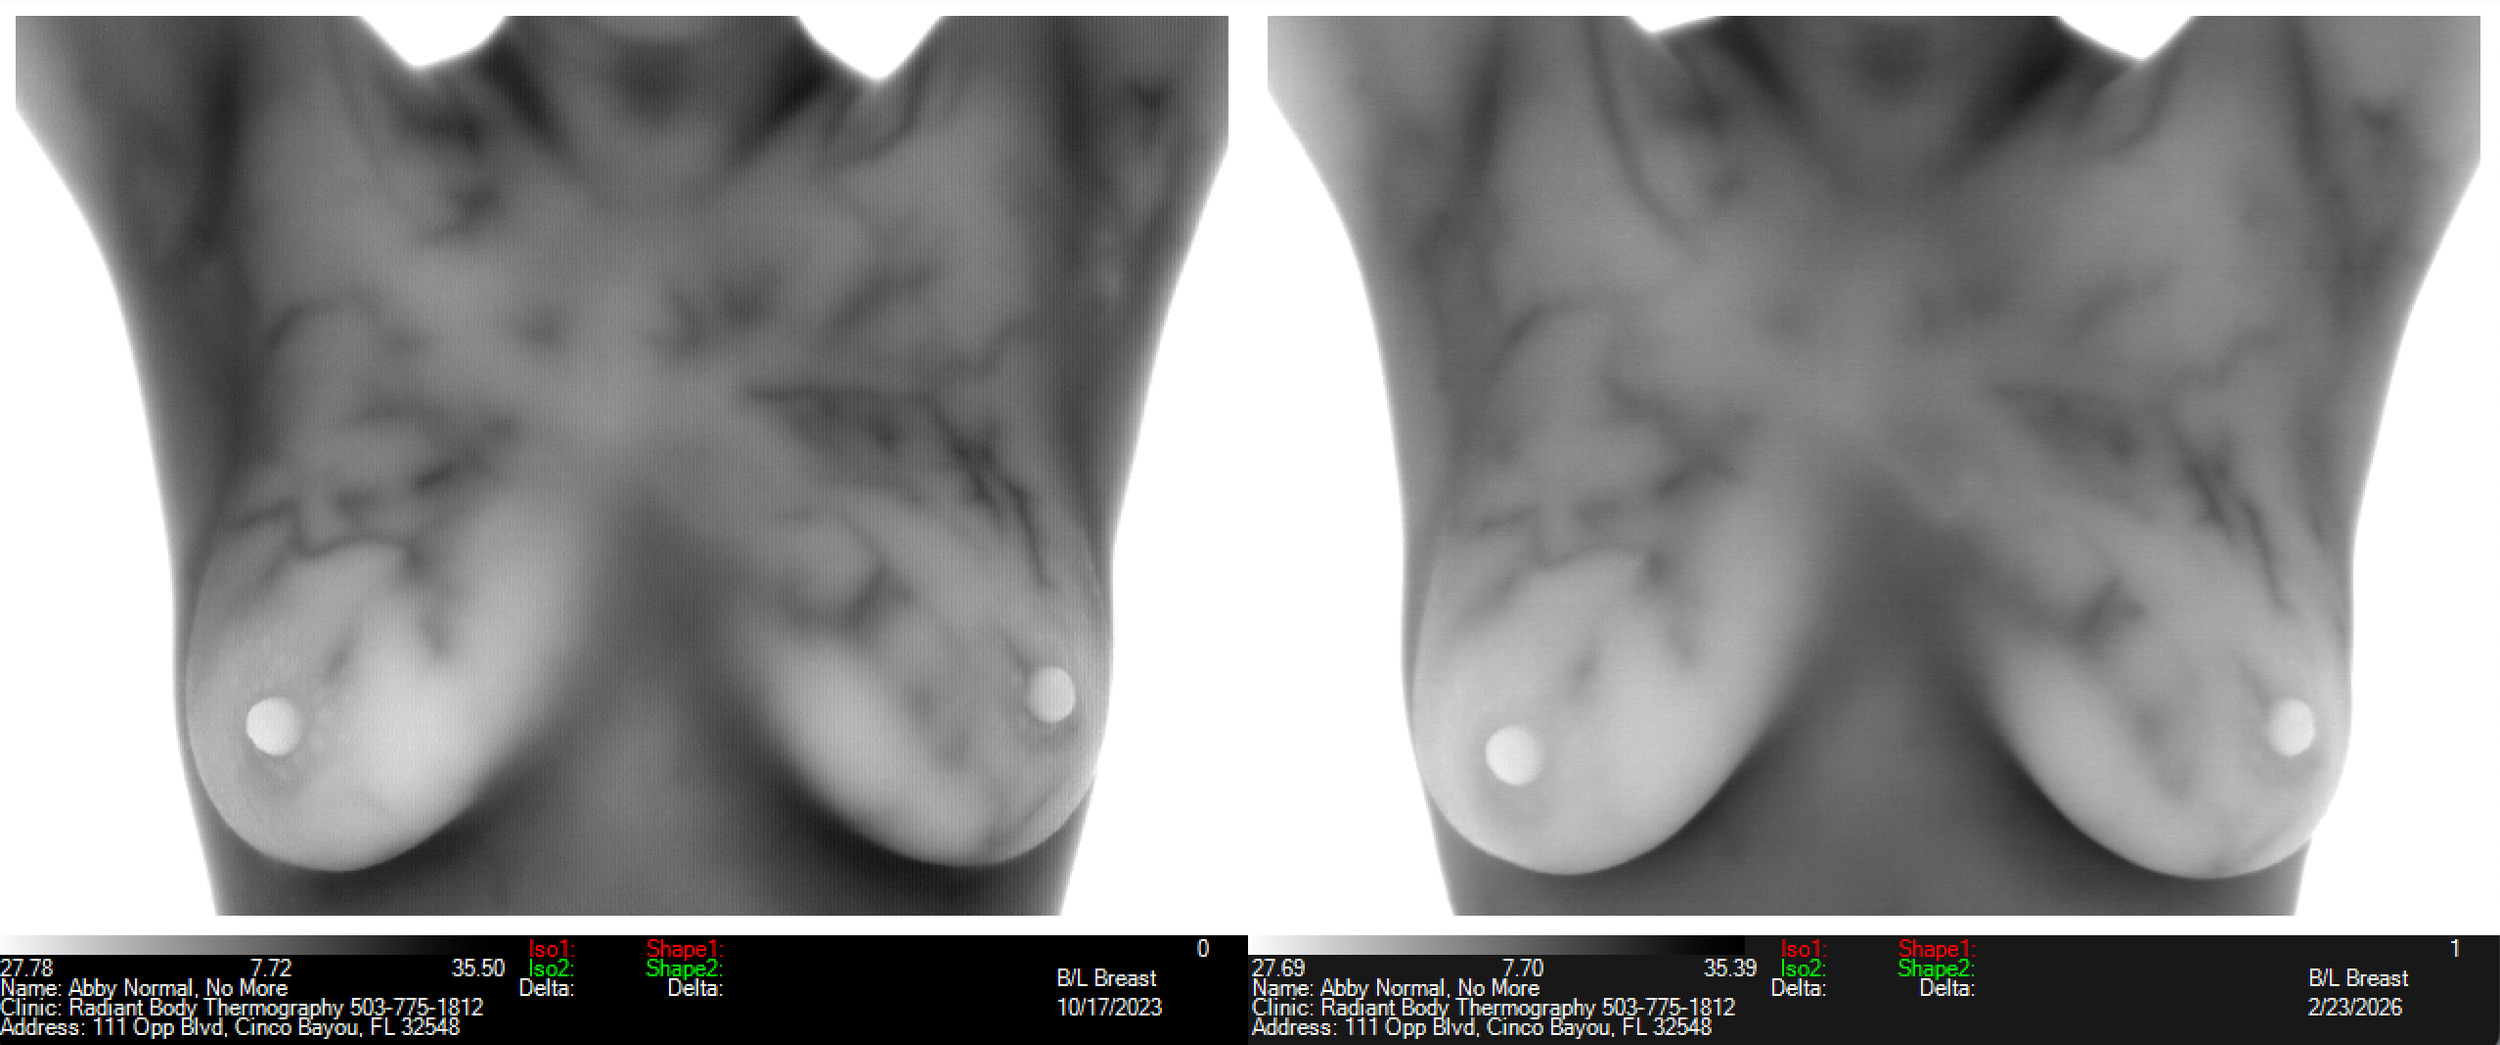

ABNORMAL Left Breast REVERSED Plus "Significant Improvement" in the Estrogen Pattern!!!

This client had an abnormal left breast for several years! All images of left breast below are “abnormal” (TH4) except the ones on the far right of each group with date of Feb 2026. It wasn’t getting worse but wasn’t getting better either, plus she had had the pattern suggesting estrogen dominance for all those years too, going back to 2018!

Lighter whiter breast as the estrogen pattern lessens - far right image shows “significant improvement”

Black is the coldest color (left end) and white (right end) is the hottest hue with this color scale.

Clearly more symmetry in the far right image - she’s no longer losing her light/heat in her left breast!